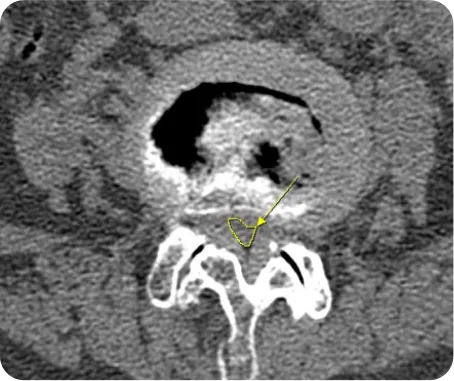

CT *

골절 및 변형의 정확한 양상을 입체적으로 파악 및 골절 이후 뼈의 유합된 정도를 판단

1. 골절 및 변형의 정확한 양상을 입체적으로 파악

2. 골절 이후 뼈의 유합된 정도를 판단

3. 뼈의 여러 방향에서 절단면을 얻을 수 있어서 미세 골절 및 뼈가 겹쳐있는 부위의 골절을 진단

4. 디스크나 협착증 환자의 경우 사고로 인해 악화된 경우 CT로 확인

5. 사고의 충격으로 인한 뇌진탕 여부를 확인

▲ 허리디스크 환자의 MRI

▲ 척추관협착증 환자의 CT